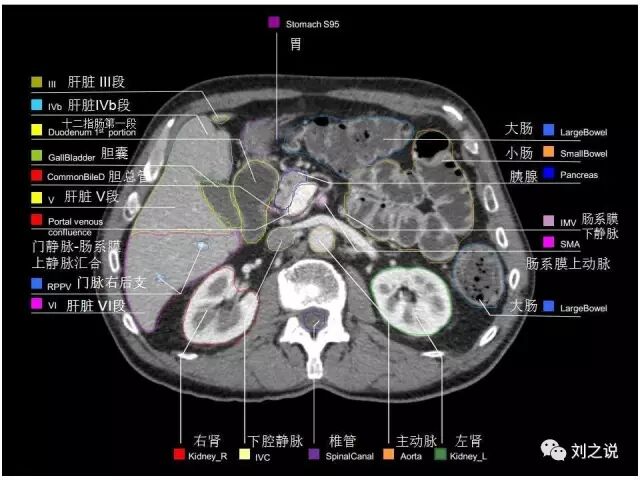

参考RTOG共识和3D-body解剖。

来源:刘之说